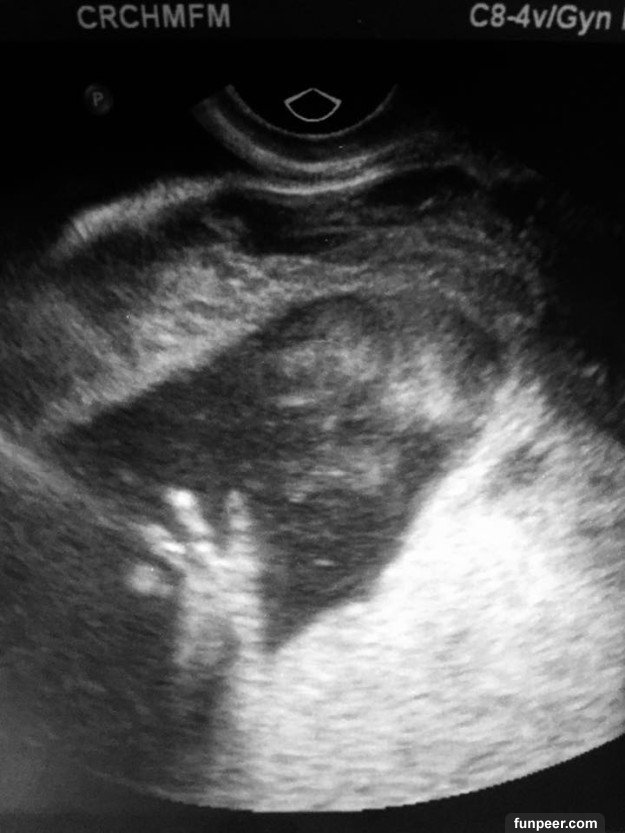

▼超音波顯示寶寶的脖子上有個異樣突起,醫生認為這是一種謎樣的「畸胎瘤」(teratoma),事情的真相只能透過核磁共振成像來進一步推測。